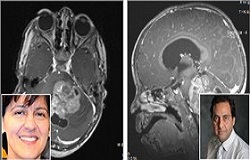

شفاآنلاین:جامعه پزشکی>درمان>تیمی از دانشمندان دانشگاه تگزاس به همراه «مریم فولادی» محقق ایرانی از مرکز پزشکی بیمارستان کودکان سینسیناتی امریکا و «جواد نظریان»، استادیار دانشگاه جورج واشنگتن، با استفاده از مدل‌های ویژه، کارآیی یک درمان هدفمند دارویی را بر روی نوعی سلول‌ سرطانی مغز کودکان بررسی کردند.

به گزارش شفا آنلاین : شاید بیماری Diffuse Intrinsic Pontine Glioma) DIPG) یکی از اشکال کمتر شناخته‌شده سرطان باشد، اما این نوع سرطان ساقه مغز، سالانه بر 200 تا 400 کودک در ایالات متحده اثر می‌گذارد و پنج سال پس از تشخیص آن، بیماران، کمتر از یک درصد شانس زنده‌ماندن دارند؛ در این میان، پرتودرمانی فقط تسکین موقتی برای این بیماری به شمار می‌آید.